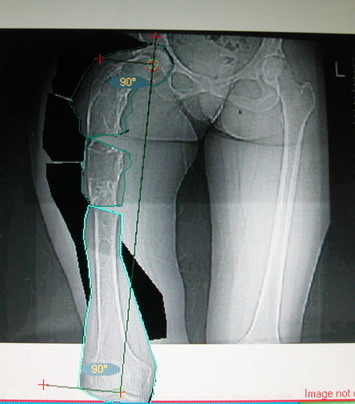

Возможна аппаратная коррекция оси с формированием клиновидного регенерата, которая решила бы и проблему укорочения (что, впрочем, нужно уточнить по схеме, сделанной по рентгенограмме с хорошим захватом смежных суставов - схемка по присланному снимку в приложении). По окончании коррекции - блокируемый стержень, который и сократит время пребывания в аппарате, и вообще возврата к нормальной жизни, а также будет мерой профилактики патологических переломов.

А может быть, если при планировании выяснится, что "открытый клин" решает все проблемы, и есть достаточное приведение в тазобедренном суставе, пойти на одномоментную операцию - чрескожная поперечная остеотомия на вершине деформации и закрытый интрамедуллярный остеосинтез.

Собственно сустав не беспокоит, объем движений полный. По скиаграммам получается, что достаточно одной остеотомии на вершине деформации, чтобы восстановить длину и вывести коленный сустав в нужное положение.

Т.к. укорочение 7 см, то начинать будем с соеотомии и коррекции аппаратом. Спасибо

На мой взгляд, для того, чтобы правильно исправить данную деформацию, необходимо обследование больного, которое должно включить в себя, помимо осмотра: 1. Рентгенограммы ( передне-задние и боковые)нижних конечностей на всю длину стоя . 2. Компьютерная томография для измерения длины нижних конечностей. 3. Комьютерная томография тазобедоенных, коленных и голеностопных суставов для измерения углов антеверсии тазобедренных суставов и ротации голеней. Это тот минимум, который должен входить в предоперационное обследование каждого больного с тяжёлыми формами деформаций конечностей.

Поскольку в данном случае имеется дело с довольно большой деформацией с укорочением, одномоментная её устранение с внутренней фиксацией, чревато с одной стороны неправильной коррекцией, с другой, нейроваскулярными осложнениями.

Моё мнение, что двойная остеотомия бедра с аппаратом Илизарова + Гексаподный механизм, или Тэйлора, В данной ситуации является методом выбора. Я очень извеняюсь за качество прилагаемых снимков, в которых я постарался отразить разницу междe одной и двумя остеотомиями бедра.